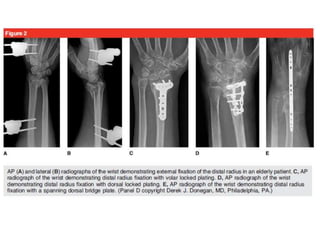

Reducción abierta + Fijación Interna

Distal Radius Fractures: Approaches, Indications, and Techniques. Current concept. Ram K. Alluri. 2016 by the American Society for Surgery of the Hand.

Abordaje

Reducción abierta placa dorsal

• Complicaciones del tendón extensor,

incluyendo irritación, sinovitis,

atrición y tendón

ruptura

• El colgajo se inicia justo cubital al

tubérculo de Lister y se eleva

para exponer el EPL y los tendones

de la cuarta

compartimiento

• Colocación de la placa puede ser

facilitada por la eliminación de la

Lister

Reducción abierta placa volar